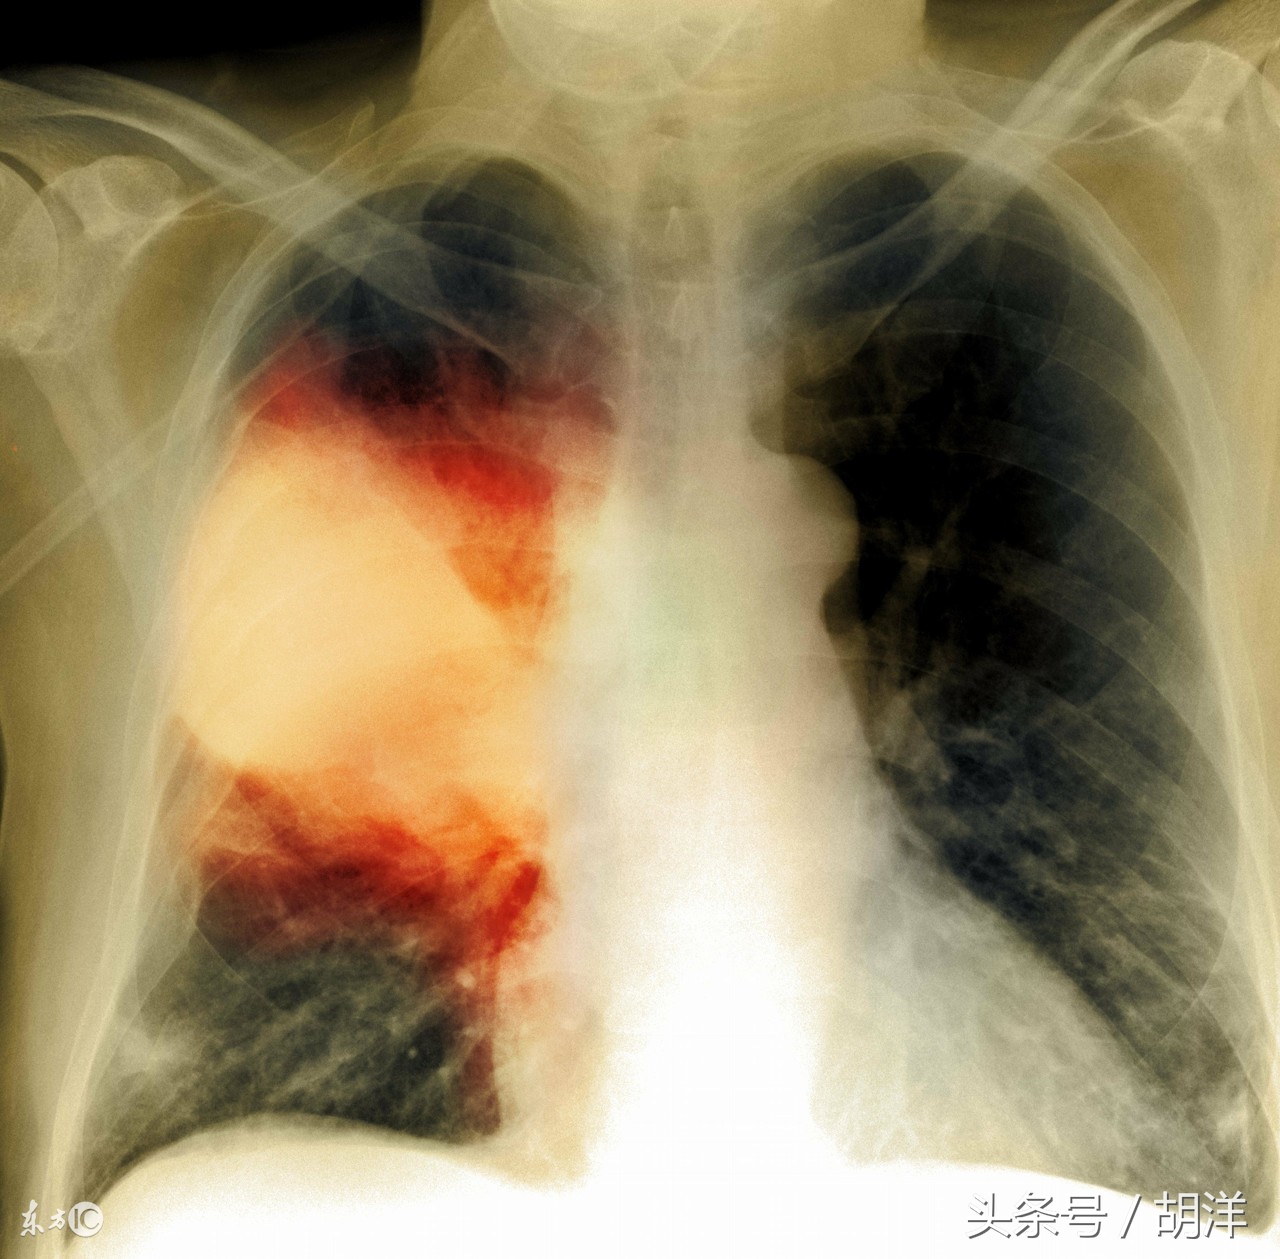

支气管扩张最重要的症状就是严重的咳嗽和大量的咳痰,严重时还伴有发热,患者的痰液具有特征性,一般为大量黄色或者绿色粘液痰,一天能咳出100ml,积在一起静置后痰液会自然分成三层,如果有这样的症状基本上可以确定为支气管扩张。

当支气管扩张引起感染甚至肺炎时,则需要使用抗生素抗感染治疗,在使用强力抗生素的时候一定要注意兼顾绿脓杆菌,因为该菌是支气管扩张常见的定植菌,也是引起咳绿痰的主要细菌,一般的抗生素对其无效。